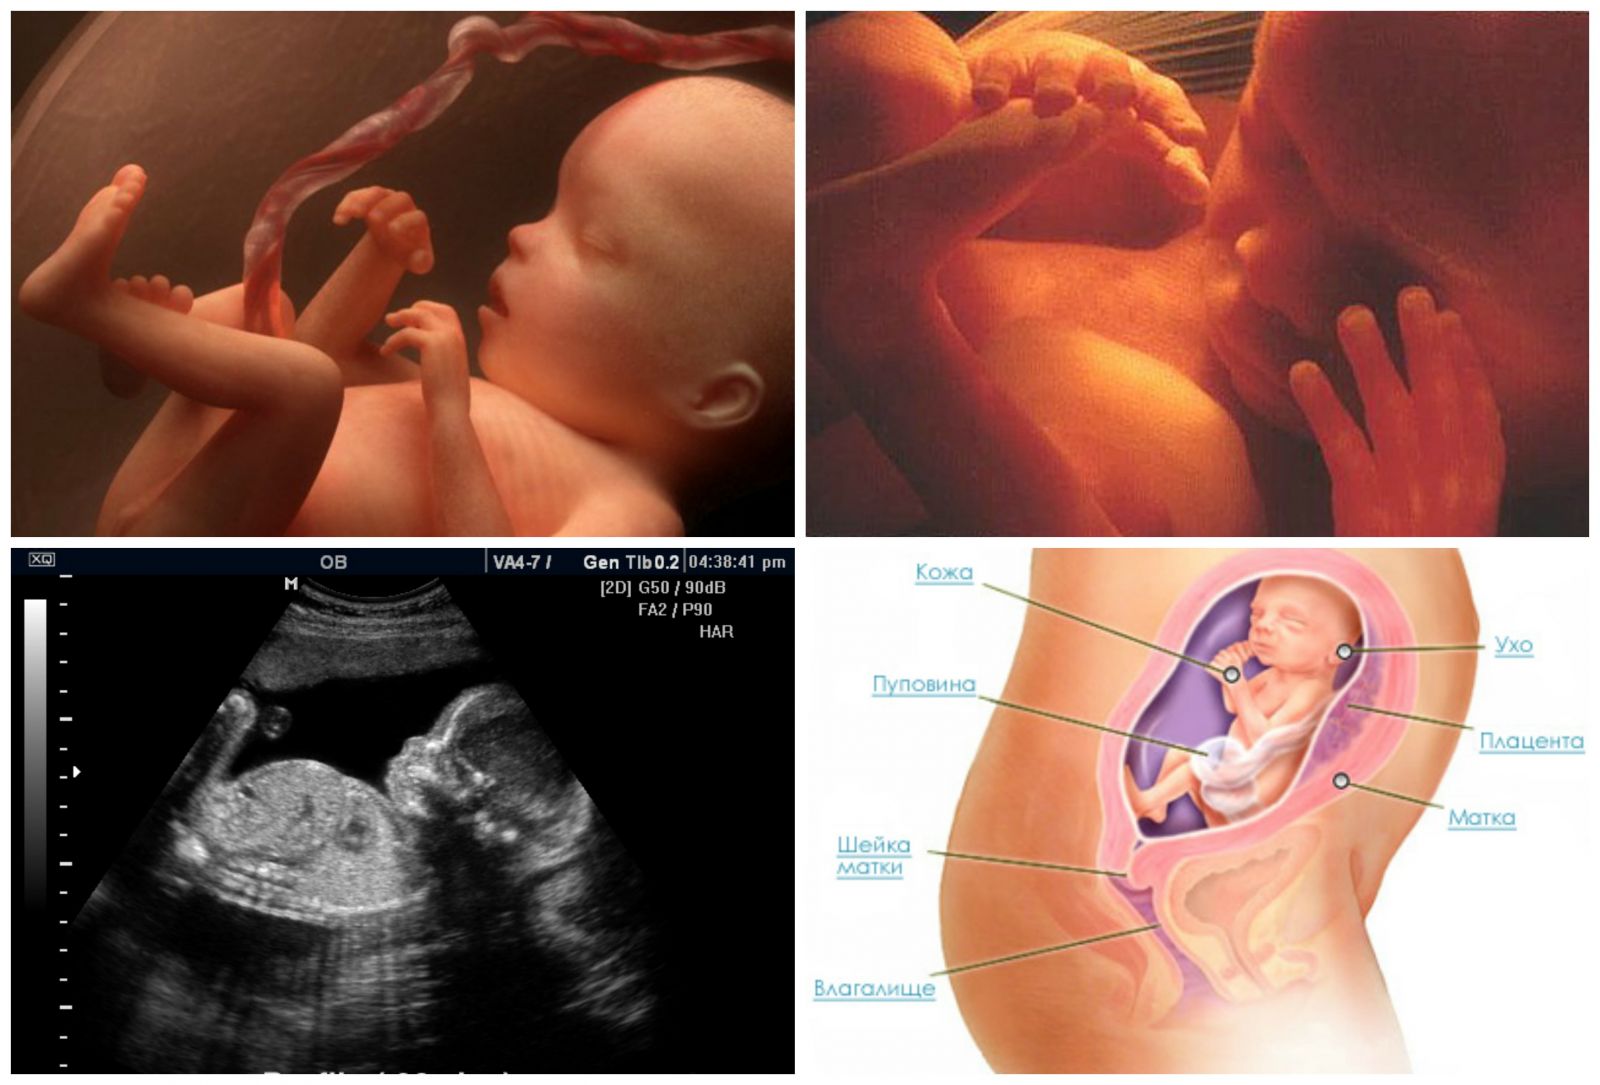

25 недель беременности: Как выглядит будущий малыш

Раздел: Образы вокруг